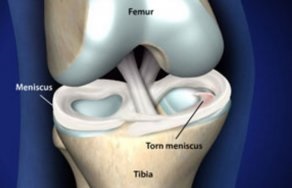

O ruptură de menisc a genunchiului - un prejudiciu popular printre dansatori, jucători de tenis, jucători de fotbal și alți sportivi implicați într-un sport de echipă. Cu toate acestea, o astfel de problemă se poate face pe oameni destul de departe de sport, a cărui.

Deteriorarea meniscul în articulația genunchiului - o boală foarte frecvente. Aceasta boala sportivi predispuse și oameni, lucrătorilor cu privire la activitatea fizică. Deteriorarea meniscului sunt cartilajului decalaj. leziuni genunchi sunt separate.

prejudiciu Menisc ocupă primul loc printre cele mai frecvente leziuni ale articulației genunchiului.

Leziunile pot implica regiunea exterioară și interioară a meniscului. Cel mai adesea astfel de leziuni apar la barbati, in special sportivi.

prejudiciu Menisc poate parea marja, sparge posterioare sau anterioare coarne mezhmeniskovyh ruptura de ligamente.

Tratamentul depinde în întregime de gravitatea prejudiciului poate fi un conservator și operațional.